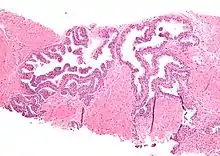

Micrograph showing high-grade prostatic intraepithelial neoplasia. H&E stain.

High-grade prostatic intraepithelial neoplasia (HGPIN) is an abnormality of prostatic glands and believed to precede the development of prostate adenocarcinoma (the most common form of prostate cancer).[1][2]

It may be referred to simply as prostatic intraepithelial neoplasia (PIN). It is considered to be a pre-malignancy, or carcinoma in situ, of the prostatic glands.

Microscopically, PIN is a collection of irregular, atypical epithelial cells. The architecture of the glands and ducts remains normal. The epithelial cells proliferate and crowding results in a pseudo-multilayer appearance. They remain fully contained within a prostate acinus (the berry-shaped termination of a gland, where the secretion is produced) or duct. The latter can be demonstrated with special staining techniques (immunohistochemistry for cytokeratins) to identify the basal cells forming the supporting layer of the acinus. In prostate cancer, the abnormal cells spread beyond the boundaries of the acinus and form clusters without basal cells. In HGPIN, the basal cell layer is disrupted but present. PIN is primarily found in the peripheral zone of the prostate (75-80%), rarely in the transition zone (10-15%) and very rarely in the central zone (5%), a distribution that parallels the zonal distribution for prostate carcinoma.[7]

Several architectural variants of PIN have been described, and many cases have multiple patterns. The main ones are tufting, micropapillary, cribriform, and flat. Although these different appearances may cause confusion with other conditions, they have not been found to be of clinical importance. Rarer types are signet-ring-cell, small-cell-neuroendocrine, mucinous, foamy, inverted, and with squamous differentiation.[3]